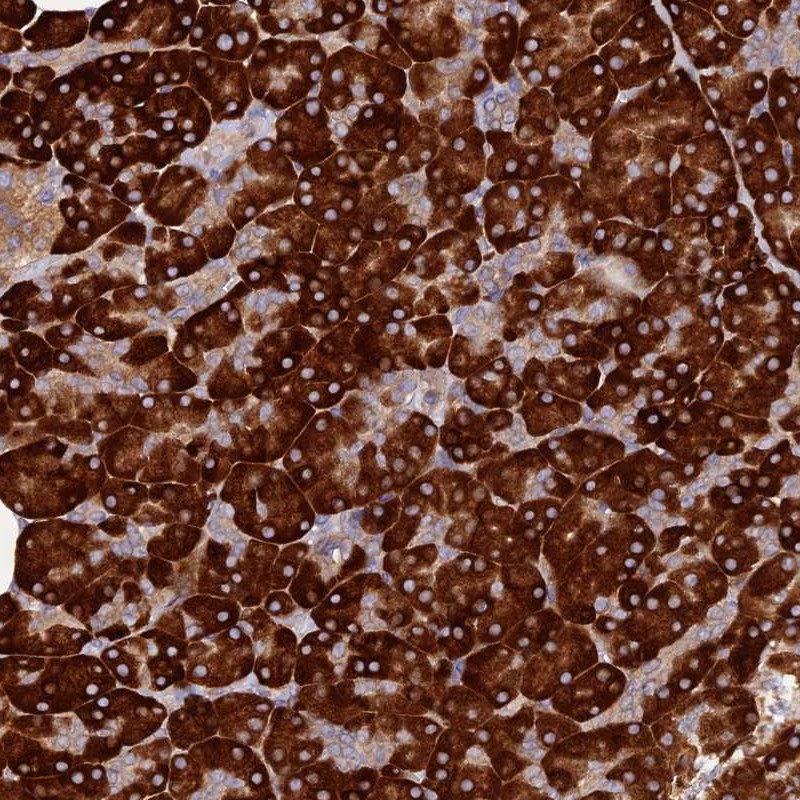

Immunohistochemical staining of human pancreas shows strong cytoplasmic positivity in exocrine glandular cells.